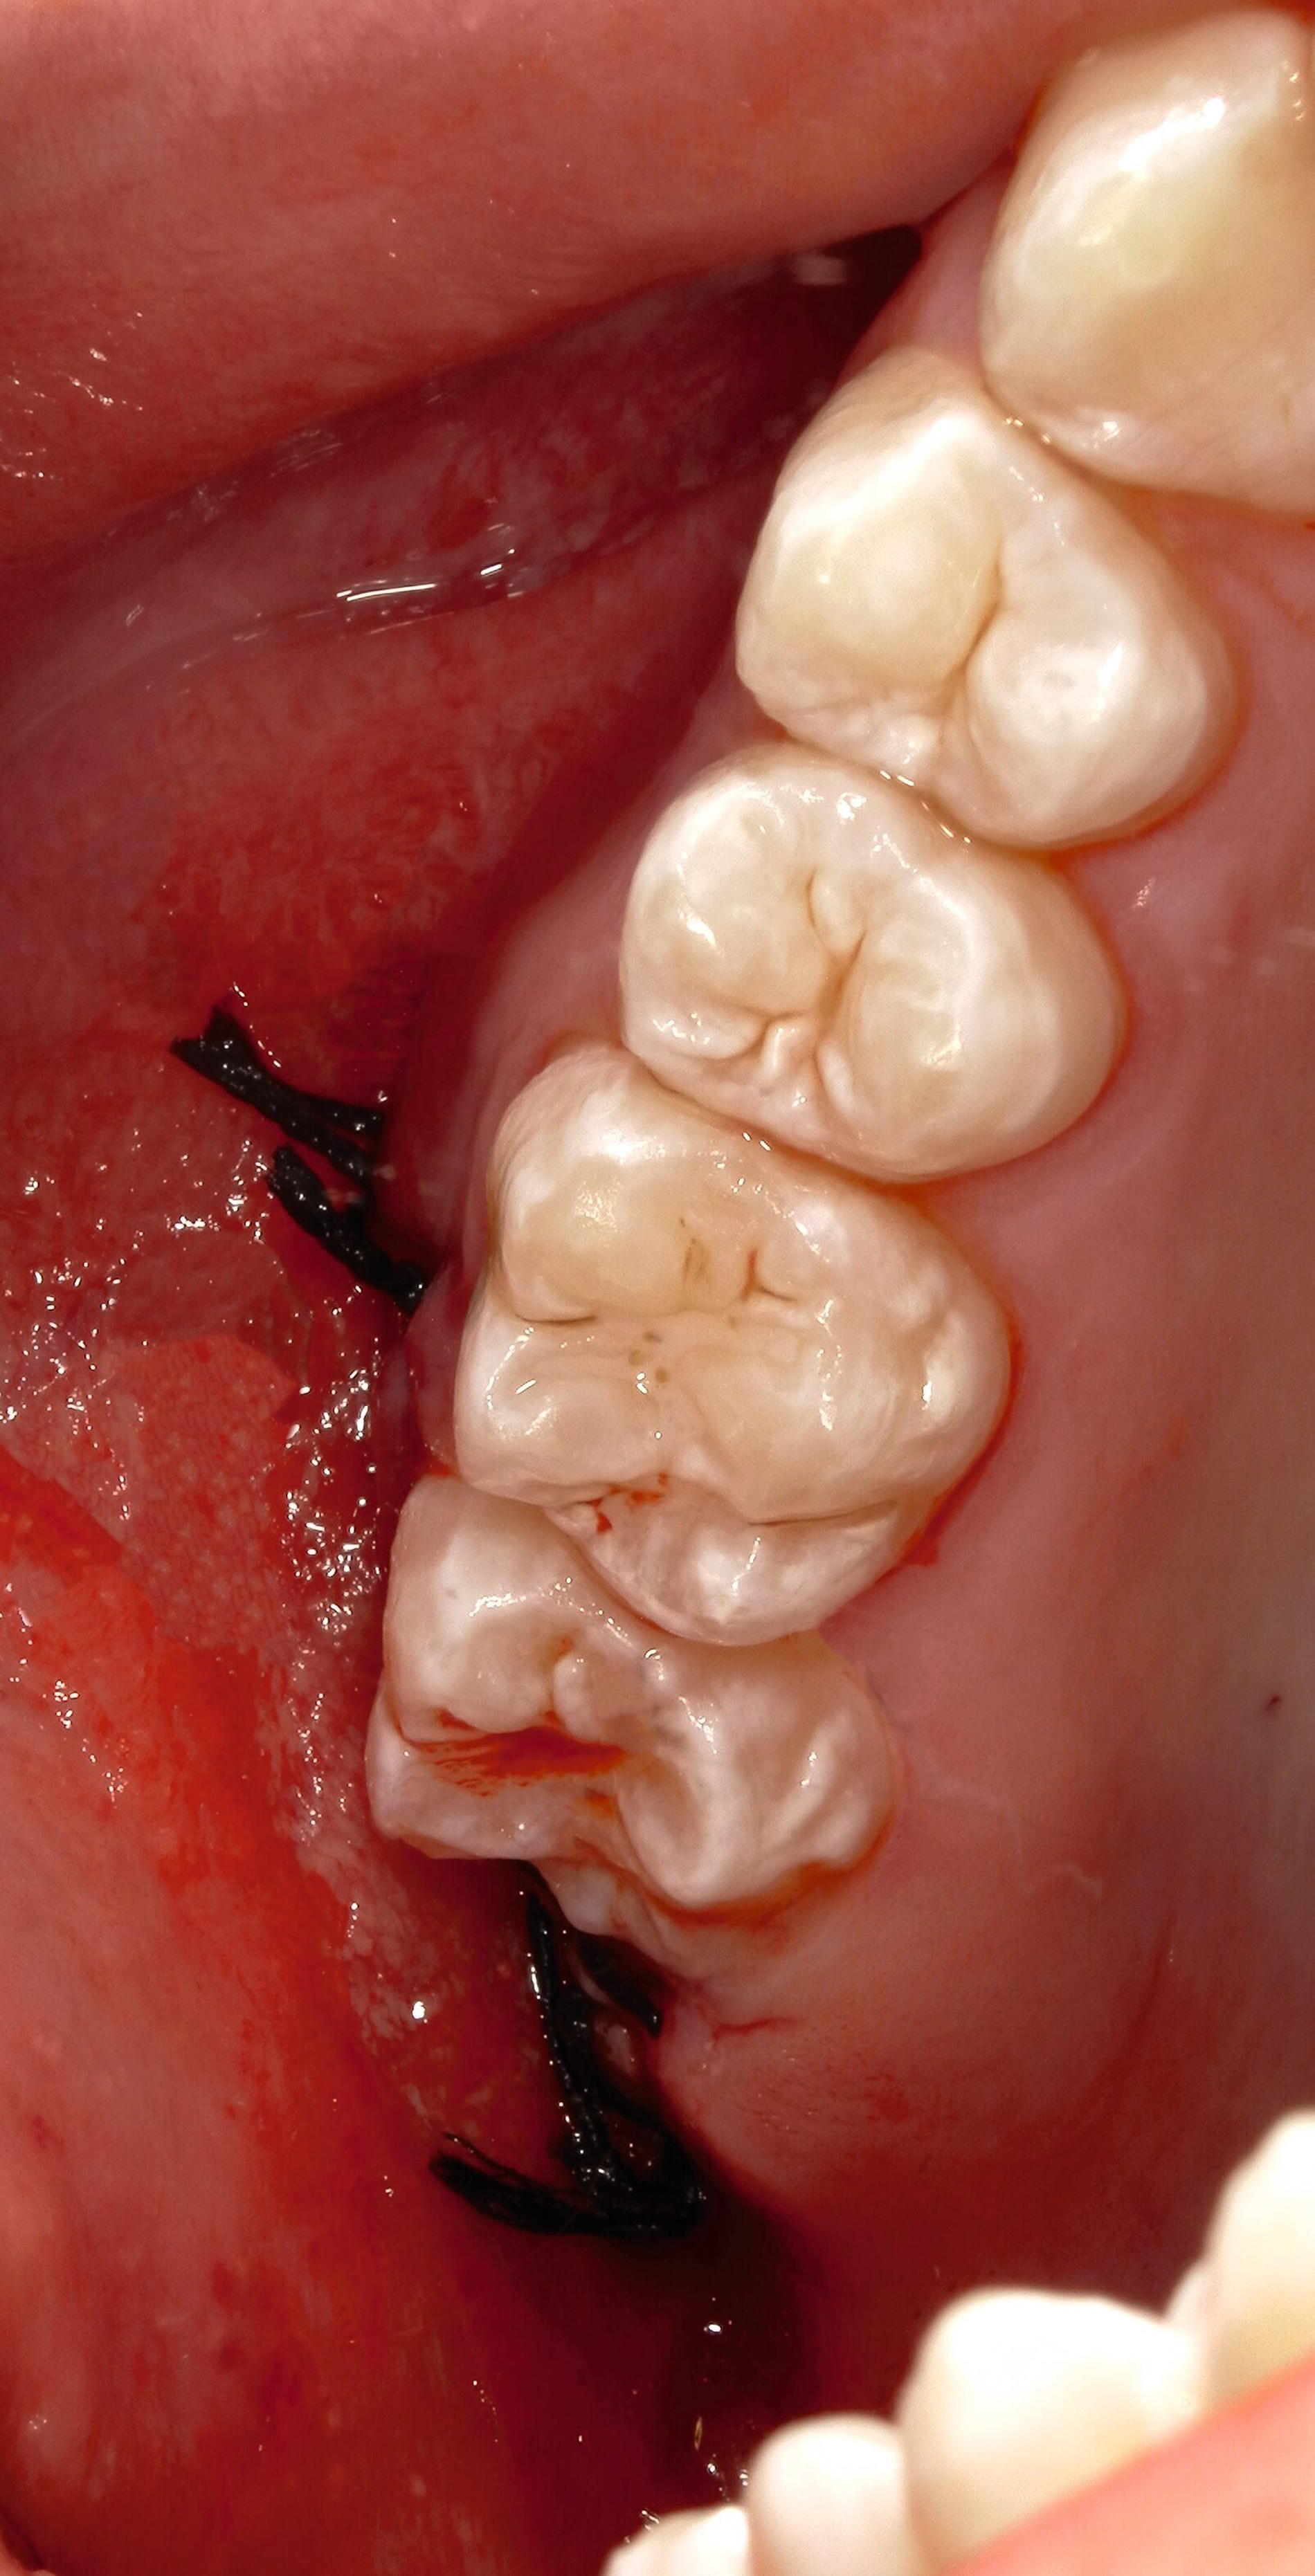

Sowohl im Unter- als auch im Oberkiefer wird letztlich ein primärer, adaptierender Wundverschluss durchgeführt (Abbildungen 12 und 15) mit Einzelknopfnähten entlang der Schnittführung, mit Beginn an der mesialen Entlastung. Dabei wird das Nahtmaterial in monofil und polyfil, synthetisch und natürlich, resorbierbar und nicht-resorbierbar, beschichtet und unbeschichtet eingeteilt [Faris et al., 2022; Minozzi et al., 2009].

Zum Wundverschluss eignen sich nicht resorbierbare, monofile, synthetische Nähte aus Polyglycolid sowie Polypropylen, da diese weniger Gewebereaktionen und mikrobielle Akkumulation hervorrufen und sich positiv auf die Wundheilung auswirken. Negativ wirken sich Seide-Fäden aus, da sie Entzündungsreaktionen auslösen und eine Affinität zur mikrobiellen Adhärenz zeigen [Dragovic et al., 2020; Faris et al., 2022].